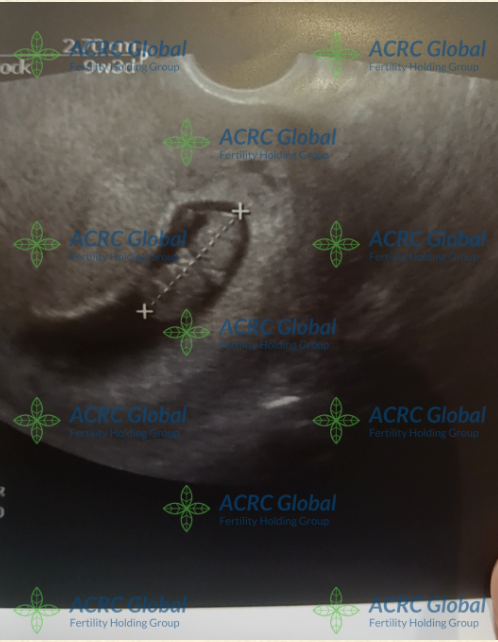

Surrogacy Update :Surrogate J’s 9-Week Ultrasound

A Tiny Life Growing Strong

We are delighted to share Surrogate J’s 9-week ultrasound this week.

The doctor pointed to the tiny developing silhouette, measuring approximately 2.7 cm, and confirmed that everything looks healthy and on track. Watching the embryo grow from a single cell into a recognizable form of life is an emotional milestone for the Intended Parents.

This ultrasound not only reassures the Intended Parents but also marks a beautiful step forward in this surrogacy journey. ACRC will continue accompanying Surrogate J through her checkups and providing updates to the Intended Parents throughout the pregnancy.